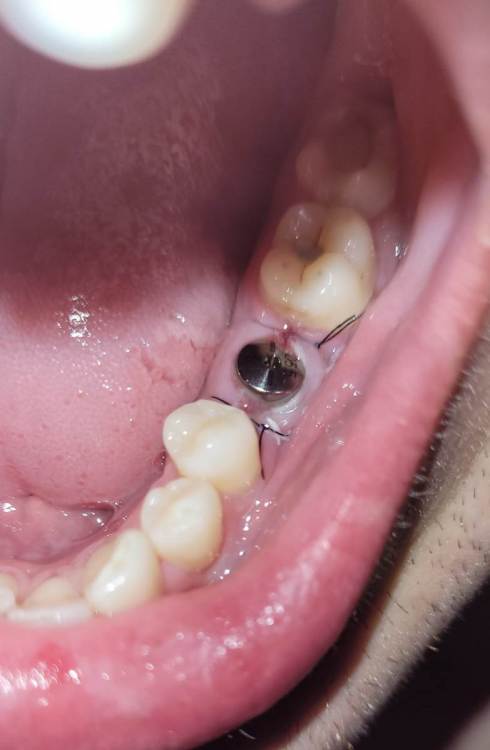

Dimarik12 Опубликовано 12 мая, 2022 Автор Поделиться Опубликовано 12 мая, 2022 @red_butler прикрепляю фото. Кажется, из-за наклона имплантата, фдм расположена сильно близко к семёрке, а с пятеркой будет щель. У меня опасения о неравномерном нагружении протеза и его преждевременной повреждении. Ps.ошибся вчера, отсутствует правая пятёрка. Ссылка на комментарий